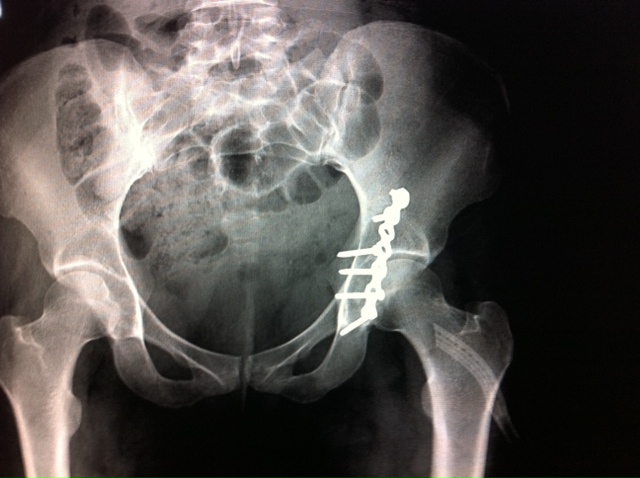

I’m heading home today with this in my hip